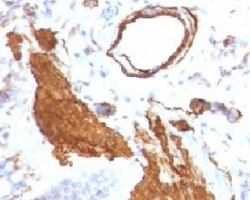

- Formalin-fixed, paraffin-embedded rat lung stained with alpha Smooth Muscle Actin antibody (ACTA2/791). This image was taken for the unmodified form of this product. Other forms have not been tested.

- Formalin-fixed, paraffin-embedded rat lung stained with alpha Smooth Muscle Actin antibody (ACTA2/791). This image was taken for the unmodified form of this product. Other forms have not been tested.

- Formalin-fixed, paraffin-embedded rat lung stained with alpha Smooth Muscle Actin antibody (ACTA2/791). This image was taken for the unmodified form of this product. Other forms have not been tested.